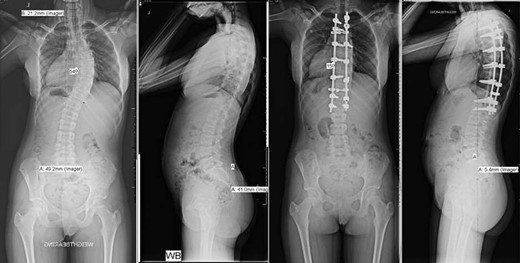

Pre- and post-operative spinal X-rays demonstrating 54° scoliosis curve, corrected with posterior fusion from T3 to L1.

She underwent a posterior spinal fusion from T3 to L1 utilizing all pedicle screw construction. Total intravenous anaesthetic was employed to allow use of intraoperative trans-cranial spinal cord monitoring. A Misonix ultrasonic bone cutter was used for the facetectomies, and two diathermy generators were available for bipolar and monopolar use. Only one suction instrument was used and no cell saver. Generous Haemostat Surgiflo was used in each pedicle following instrumentation, and Spongostan foam, Surgicel and bone wax at the osteotomy sites. To further reduce bleeding, the mean arterial pressure (MAP) was maintained <70 mmHg and a costoplasty was avoided despite the rib hump. The total operation time was 220 min with 300 mL estimated blood loss (Fig. 1).